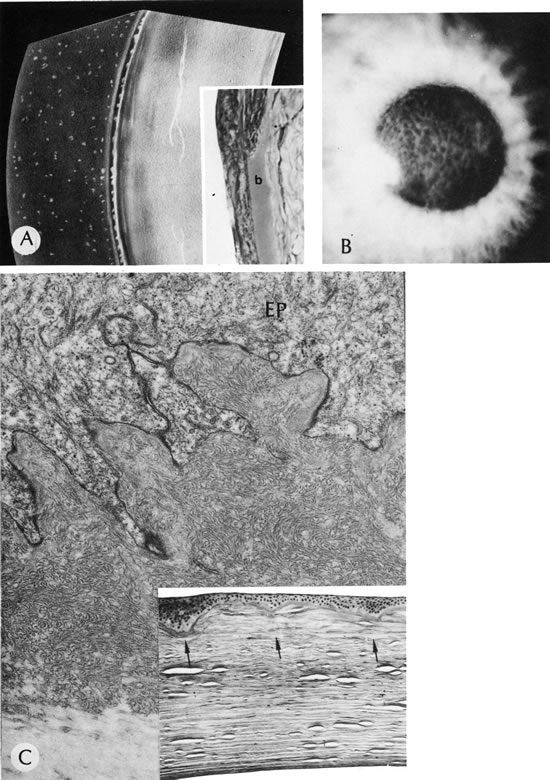

Fig. 27. Reis-Bucklers'dystrophy (corneal dystrophy of Bowman type II [CDB-II]). A. Early stage shows small, white dots in continuity with the band of relucency representing Bowman's membrane. Biopsy (inset) is oriented to correspond to drawing. Bowman's membrane (b) is destroyed at the top. B. Moderately advanced stage shows confluence of the whitish subepithelial mounds in the characteristic honeycombed pattern. C. The abundant subepithelial tissue composed of peculiar curly filaments is highly characteristic of the entity. The filaments are closely interwoven, with regions of thin basement membrane. Hemidesmosomes along the epithelial basal cell (EP) are fewer than normal. The basilar cell processes are abnormal. Inset shows degeneration of Bowman's membrane in several foci (arrows indicate membrane remnants). The thick, avascular, fibrous membrane present under the epithelium forms mounds that produce a typical honeycombed pattern in three dimensions. (Courtesy of SEI Photoarchives.) (A modified from Griffith DG, Fine BS: Light and electron microscopic observations in a superficial corneal dystrophy: Probable early Reis-Buckler's type. Am J Ophthalmol 63:1659, 1967; B and C modified from Perry HD, Fine BS, Caldwell DR: Reis-Buckler's dystrophy: A study of eight cases. Arch Ophthalmol 97:664, 1979.)

Fig. 28. Reis-Bucklers' dystrophy. A. Late-stage Reis-Bucklers' dystrophy. B. Bowman's membrane (arrow) has degenerated, and a heavy subepithelial pannus has formed. The remainder of the stroma is normal. Inset shows high magnification of the area where Bowman's membrane has been destroyed. (Courtesy of SEI Photoarchives.)